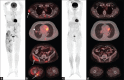

We report a rare case of nocardiosis with increased F-18 Fludeoxyglucose (F-18 FDG) uptake in widespread abscess foci of Nocardia farcinica infection in an immunocompromised patient on positron emission tomography computed tomography (PET/CT) imaging. A relatively infrequent cause of nocardiosis, N. farcinica is an opportunistic infection that may present with clinically aggressive disseminated disease. Whole-body F-18 FDG-PET/CT allows identifying the extent of disease, as well as monitoring response to therapy in patients with nocardiosis especially the disseminated form.